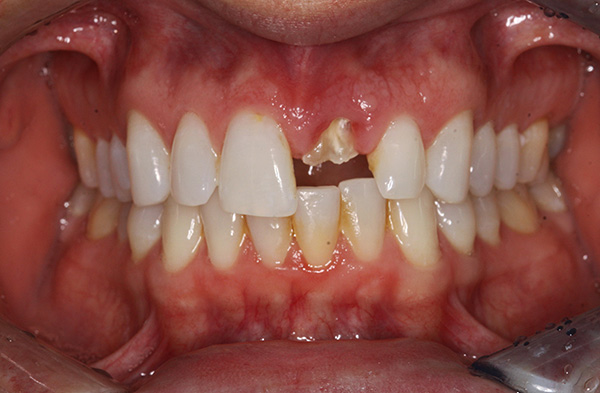

Para remoção complexa, às vezes é usada anestesia. Uma diferença característica entre uma extração complexa de dentes e uma simples, além do tempo gasto, é o uso de uma broca (para serrar um dente em pedaços, cortar um osso), parafusos, ligaduras e algumas outras ferramentas específicas (às vezes um dente é literalmente dividido em pedaços com um cinzel e um martelo).

A fotografia abaixo mostra um exemplo de um dente serrado antes da remoção em três partes usando uma broca: